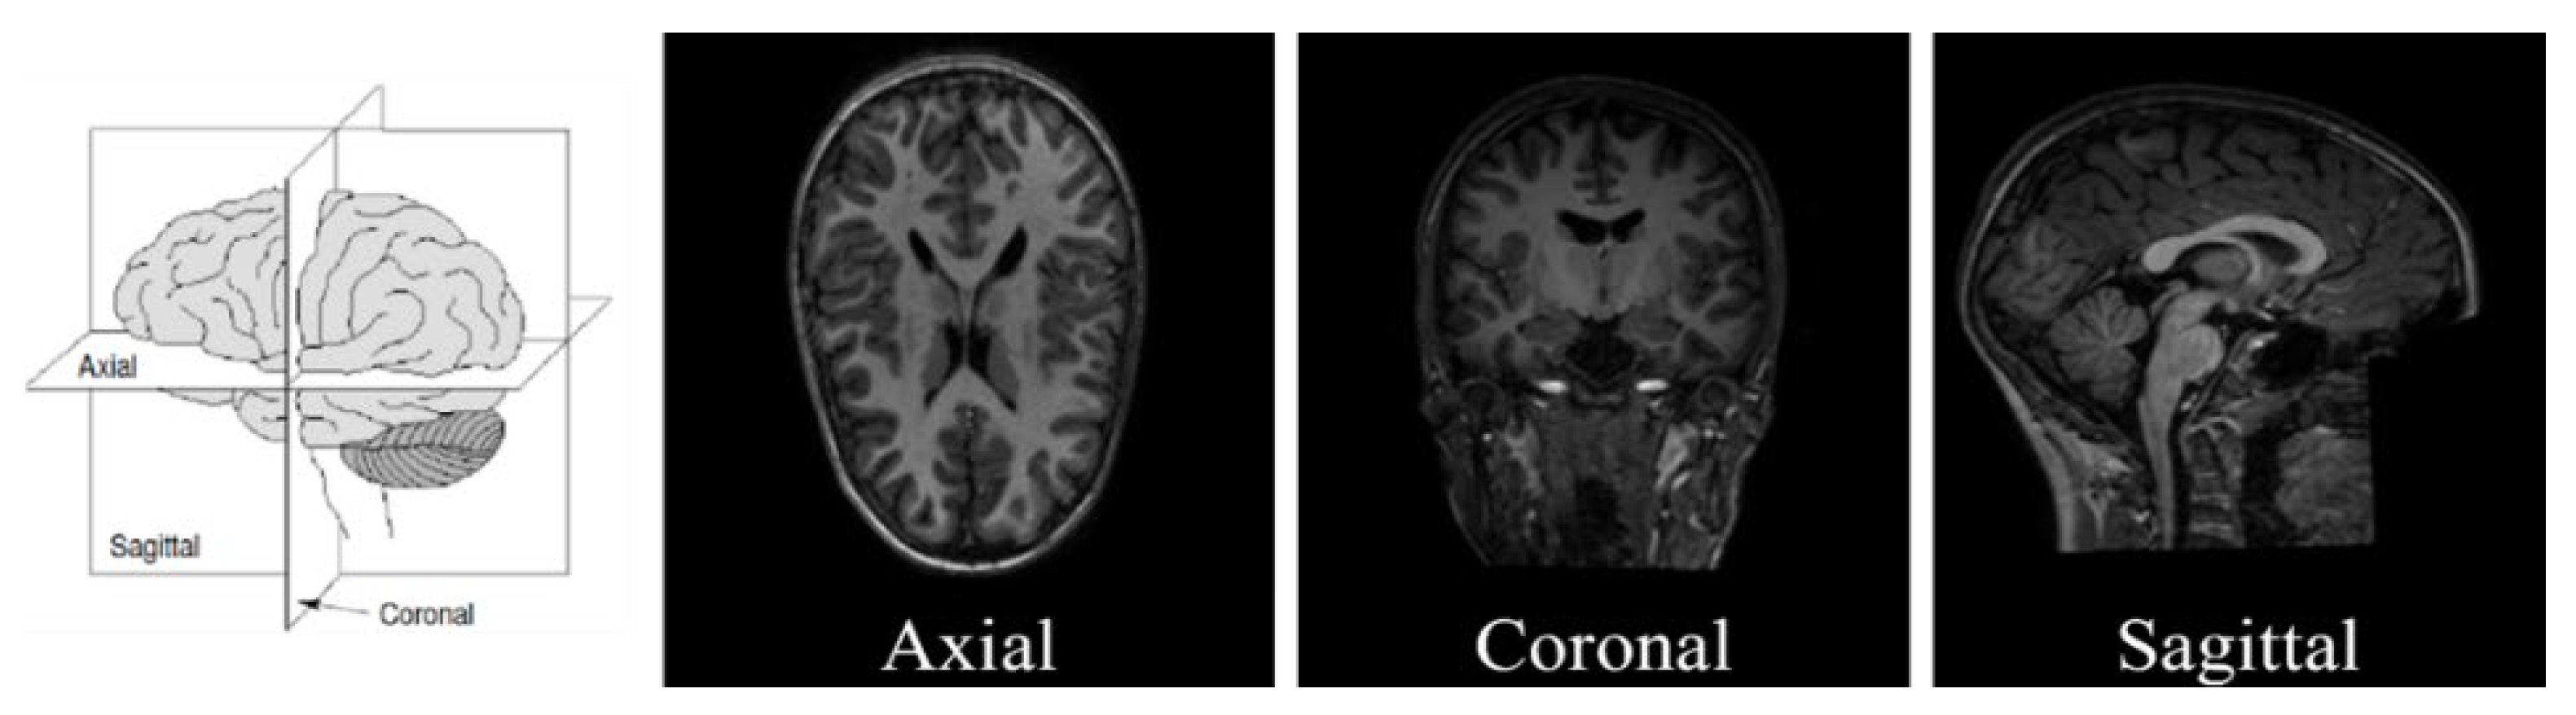

- Extracting 1, 10, and 50 slices along each brain plane (axial, sagittal, and coronal) to generate sequences of 2D images from raw 3D sMRI scans.

- Extracting 10, 30, and 50 slices along all brain planes (axial, sagittal, and coronal) to generate sequences of 3D images from raw 4D fMRI scans.

- Extracting all slices or giving some exceptions to the beginnings and the ends along all brain planes (axial, sagittal, and coronal) to generate sequences of 3D images from 3D sMRI and 4D fMRI scans.